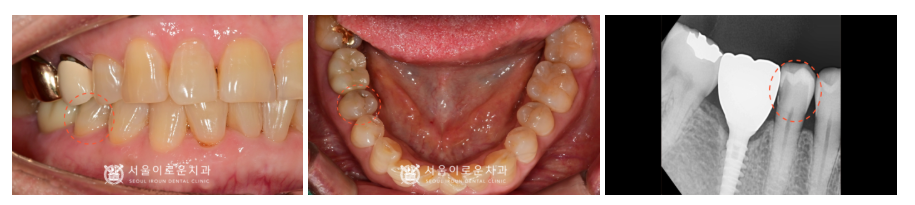

우선 위턱 왼쪽 두 번째 작은 어금니(#25)의

조각난 치아 부분을 제거 후

꼼꼼하게 신경치료를 완료한 뒤

Post(기둥)을 세워 레진으로 보강하였고,

크라운 제작을 위해 치.아를 다듬었습니다.

크라운 보철물 치료가 마무리 된 모습의

파노라마 사진과 구강 내 사진입니다.

더불어 불편감이 있으셨던

해당 치아뿐만 아니라

아래턱 오른쪽 두 번째 작은 어금니(#45)

치아 사이에 충치가 심하여

치료의 필요성에 대해서

환.자분께 설명드렸는데요.